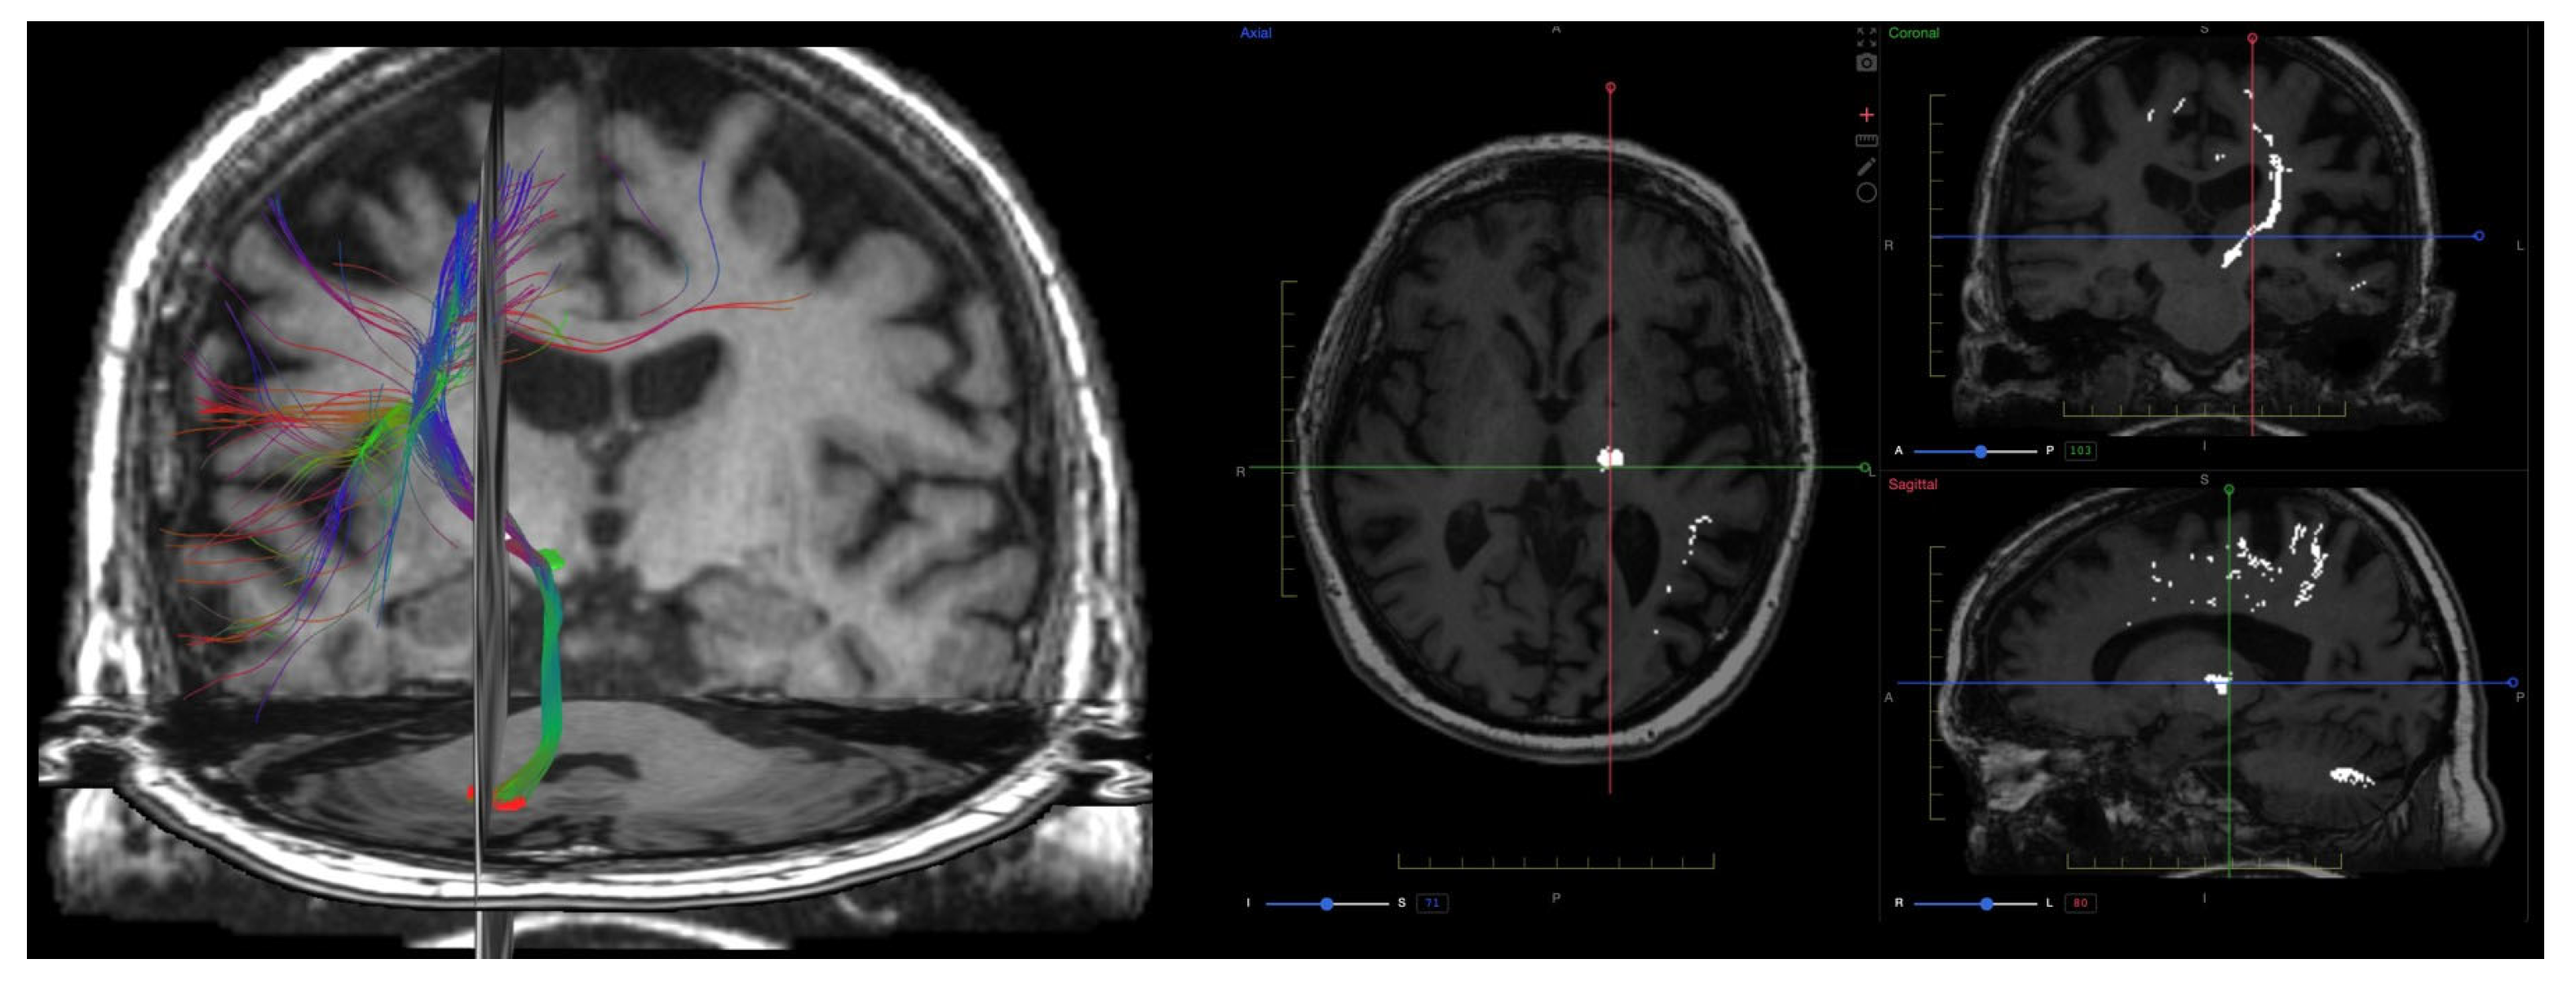

9. Diffusion Imaging (DWI, DTI, DKI)

9.1. Physics and Signal Model

9.2. Acquisition and Key Parameters

9.3. Outputs and Units

- Fractional anisotropy (FA): degree of diffusion directionality,

- Mean diffusivity (MD): average diffusivity, equivalent to ADC but derived from tensor data,

- Axial diffusivity (AD): diffusion parallel to axons,

9.4. Clinical Applications

9.5. Validation and Repeatability

9.6. Emerging Techniques and Integration

9.7. Summary and Outlook